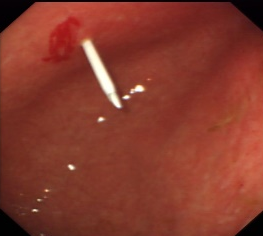

在冠脉造影和介入治疗中,医生们通常选择常规的近端桡动脉穿刺入路(手腕上方),但如果这个部位反复穿刺形成血栓、斑块或者局部瘢痕,医生无法穿刺进入怎么办?别急,近